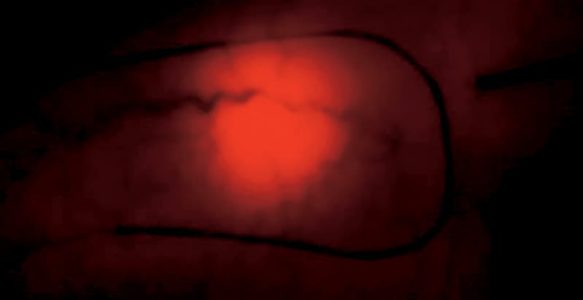

La phlébectomie tri-vex

est une technique qui remplace la phlébectomie.

A l’aide d’une petite sonde rigide motorisée introduite sous la peau, les varices sont sectionnées, fractionnées et aspirées. Le repérage des varices s’effectue par transillumination en plaçant une petite source lumineuse sous la peau.

C’est une technique plus traumatisante et plus douloureuse que la phlébectomie superficielle et qui entraîne de nombreux hématomes. Elle ne peut se réaliser que sous anesthésie générale. Elle n’est indiquée que pour de très grandes surfaces de varices quand ni l’esthétique ni le confort ne sont une priorité.